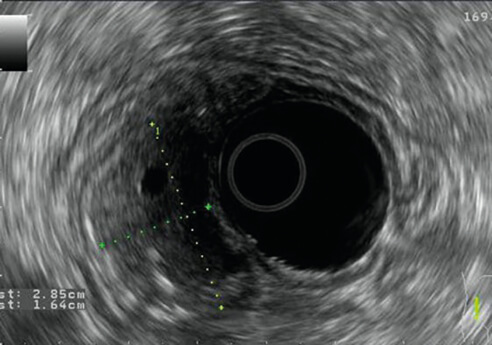

Εικόνες 1, 2: Εξελκώµενο GIST (GastroIntestinal Stromal Tumour) στοµάχου

Εικόνα 1